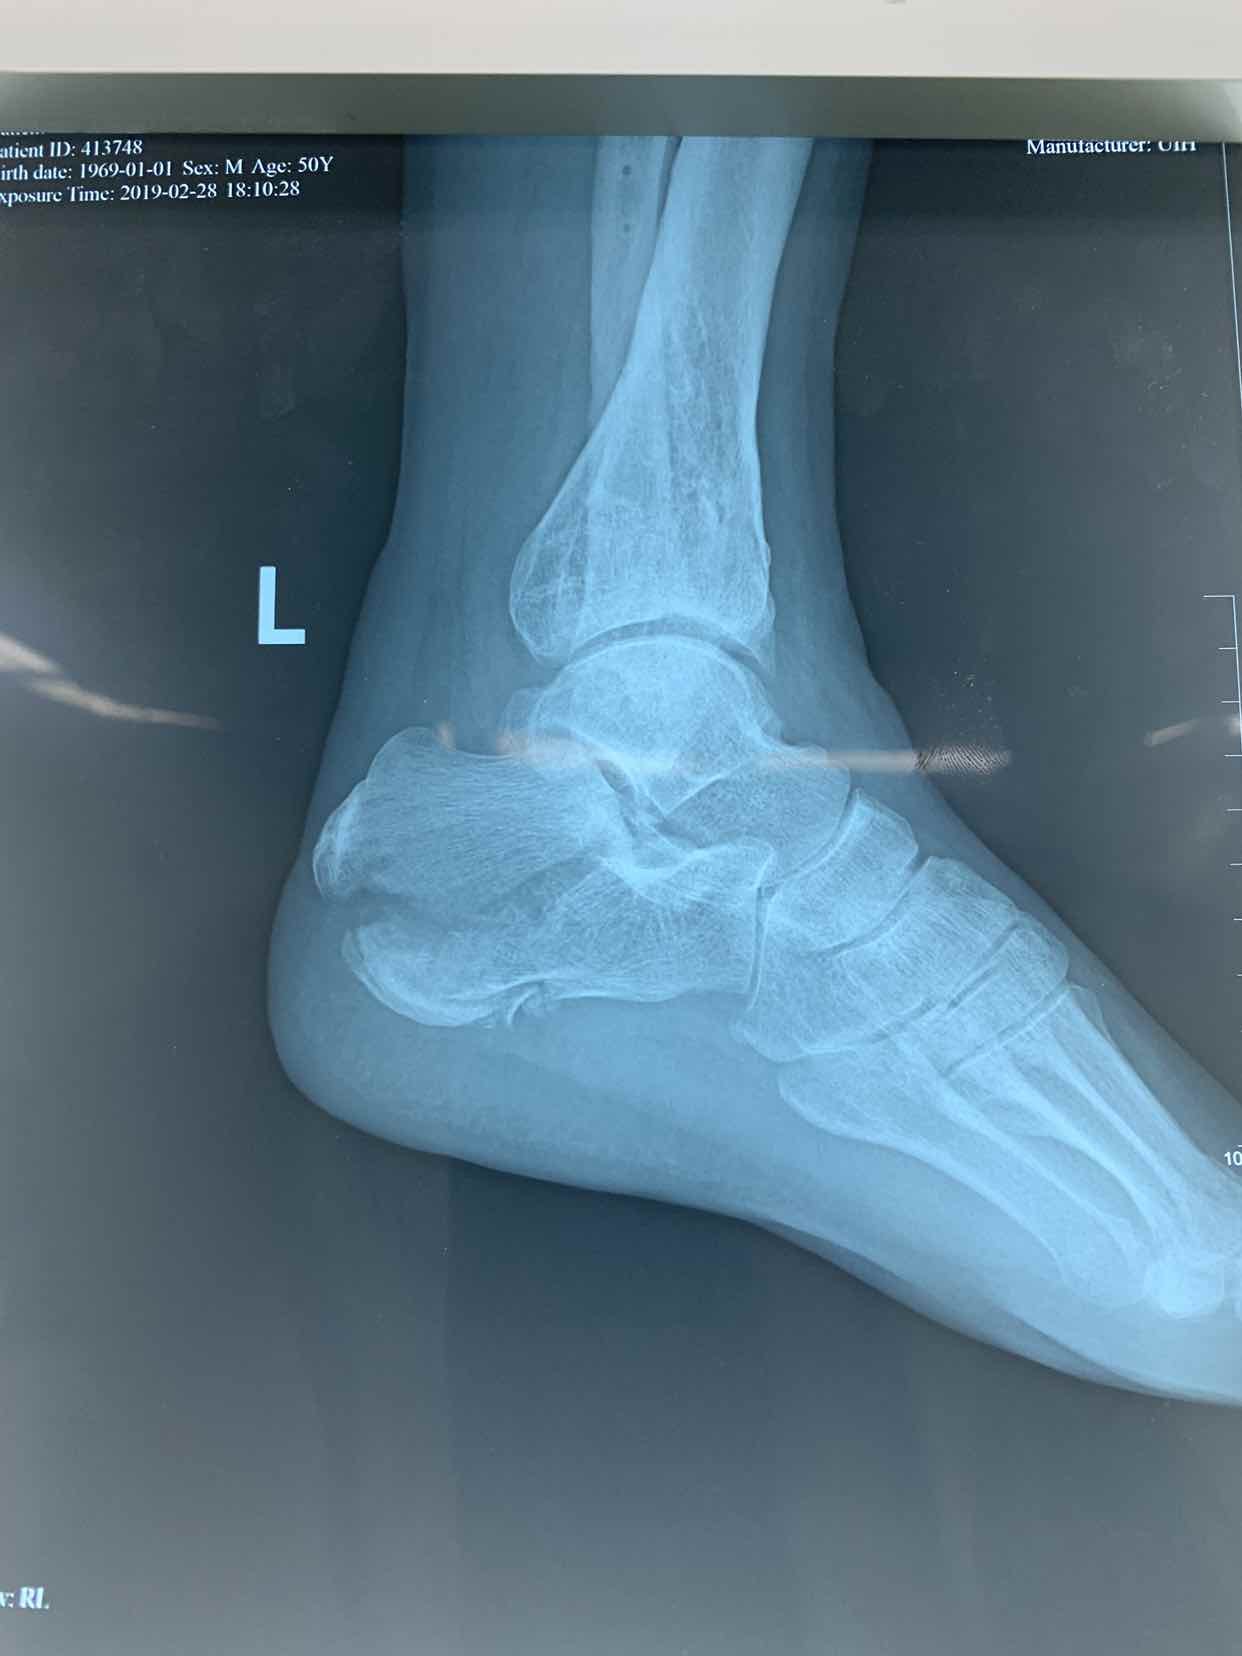

高处坠落,左跟骨粉碎骨折一例

患者因自二米高处坠落,左侧足跟肿痛畸形活动受限一小时收入院。患者于一小时前不慎自二米高处坠落。当即左侧足跟肿痛。畸形。不能下地走路。急来诊。门诊拍片提示左侧跟骨骨折。门诊以左侧跟骨骨折收入院。

查体见左侧左跟局部肿胀。足弓消失。跟骨横径增宽。局部畸形。活动受限。不能下地走路。局部皮下淤血。拍片提示左侧跟骨粉碎性骨折。断端移位。

诊断为左侧跟骨粉碎性骨折。在腰麻下行闭合复位空心钉内固定术。术后恢复较好。